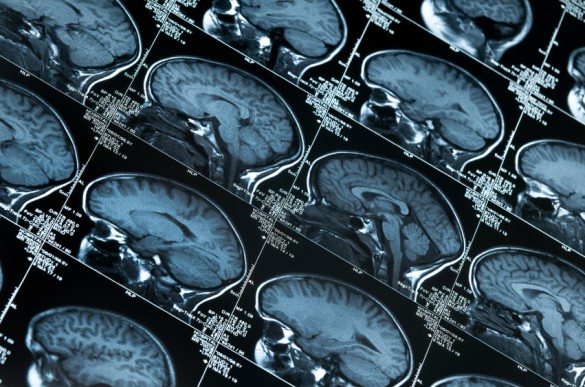

Tricia Thornton-Wells, Ph.D., assistant professor of Molecular Physiology and Biophysics, and colleagues explored the association of gene-gene interactions with neuroimaging measurements from participants in the Alzheimer’s Disease Neuroimaging Initiative. They tested the association of specific gene pairs with MRI measurements of the brain’s inferior lateral ventricles (ILV). Increasing ILV volume, which reflects neuronal degeneration in the hippocampus and entorhinal cortex, correlates with Alzheimer disease status and progression.

The investigators identified four genetic interactions associated with changes in the right ILV, and one of the four – the gene-gene pair SYNJ2–PI4KA – was also associated with changes in the left ILV. Both genes belong to the inositol phosphate signaling pathway, suggesting that disruptions in this pathway may reduce neuronal cell survival and lead to increased ventricle volumes.